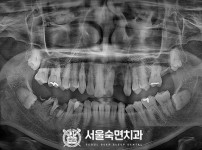

임플란트-전후사진2

치과를-선택할-때-꼭-확인하세요-서울숙면치과-임플란트-전후사진